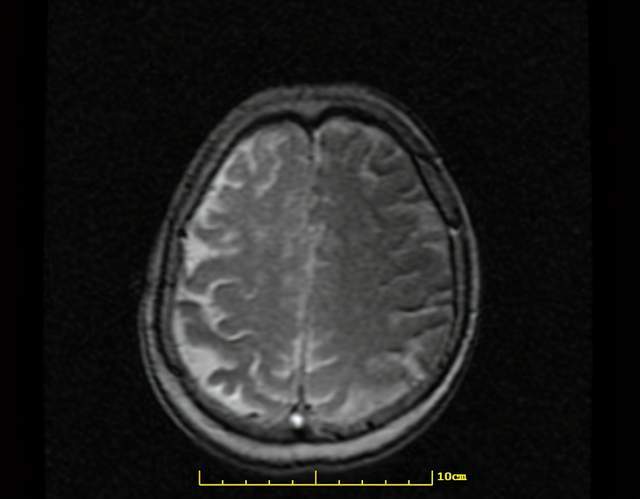

无症状脑梗可在头颅CT或MRI检查时 , 发现与脑血管分布一致的脑梗死灶或脑软化灶 , 从而确诊出该疾病 。